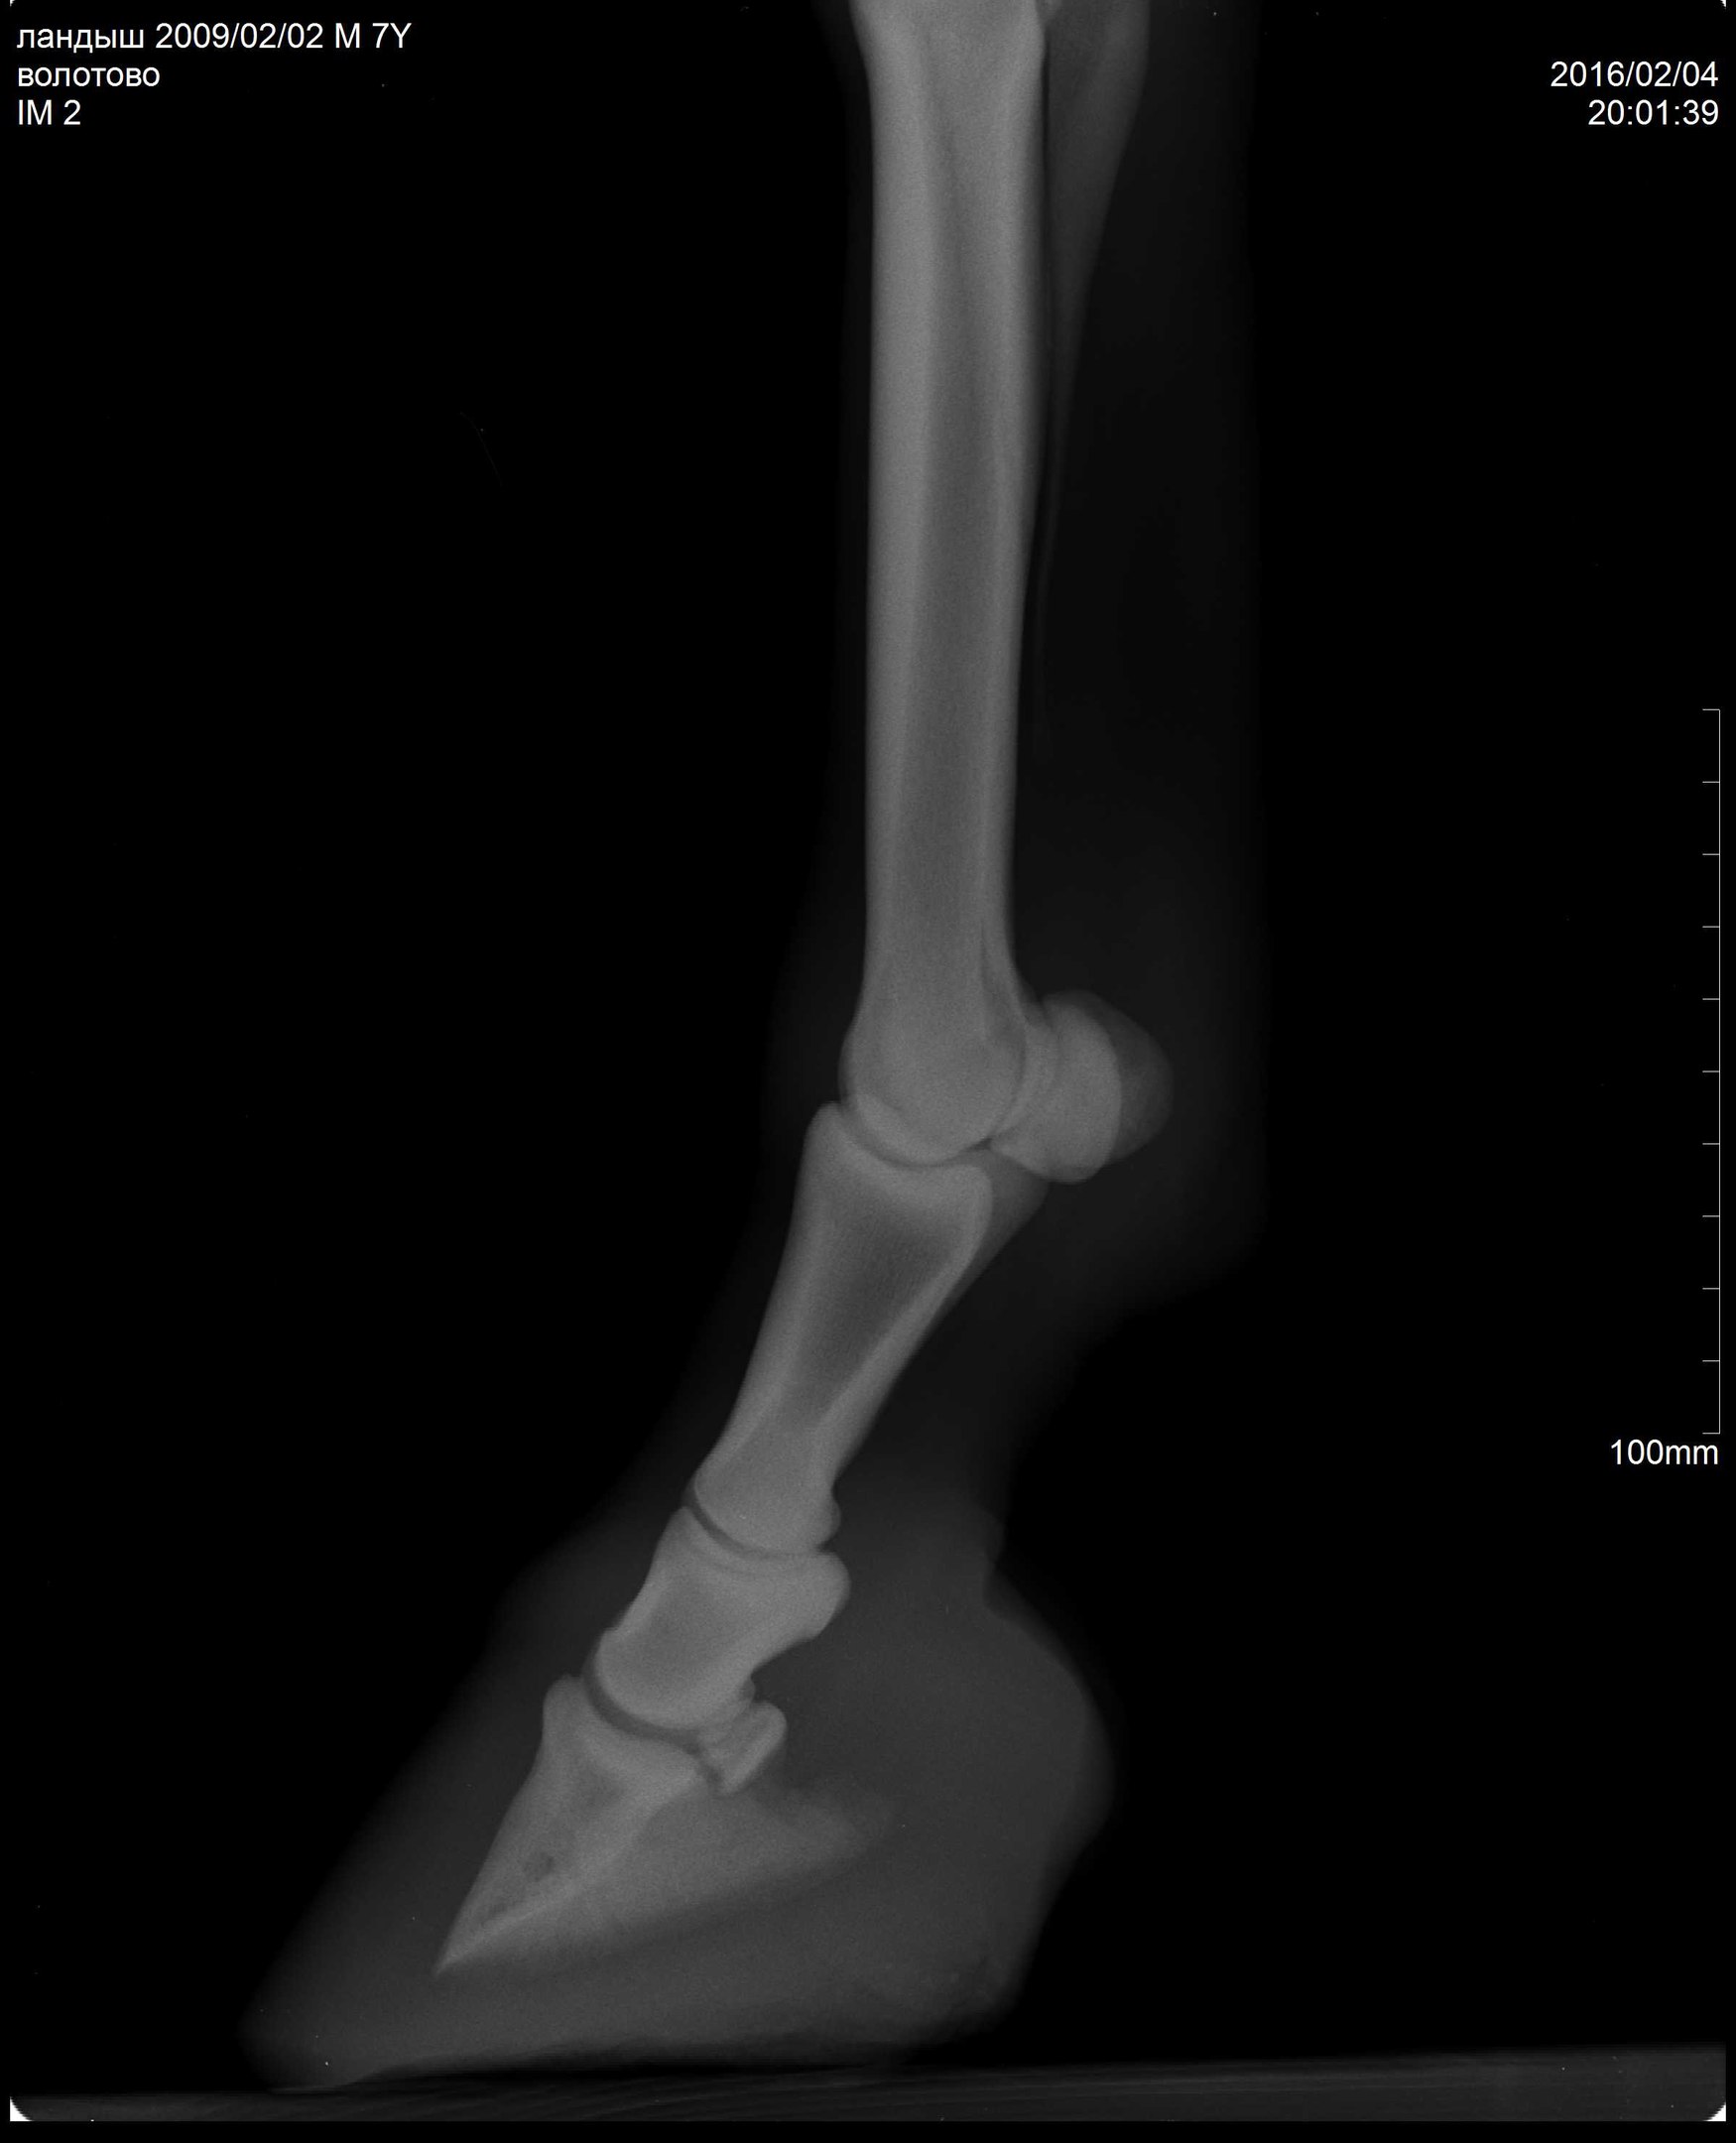

В общем, после чудесного-расчудесного лекарства Флуниджекта и замечательных обнадеживающих рентгенов пони всего лишь требовалась грамотная расчистка. Нужно было чуть изменить угол копыт, чтобы выправить копытную кость более-менее параллельно подошве (хоть в некоторых статьях я читала, что совсем необязательно эта параллельность должна быть нормой).

А тут нужна была тонкая, филигранная работа. Рентгенолог Анна мне оставила диск с программой, где можно было выверять углы, каждый миллиметр контролировать!!!! А я, конечно, со своими клещами и целью тупо на 1см понизить пятки, натворила дел (((